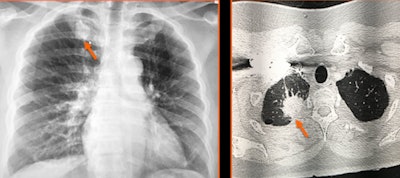

Potential missed findings include cancer, infection, pseudoaneurysm, fracture, and bowel perforation, according to an electronic exhibit at the meeting. First author Dr. Willie McClure of the David Grant USAF Medical Center at Travis Air Force Base in California and colleagues shared five cases that had obvious findings when recognized but which were not reported due to "tunnel vision" by the interpreting radiologists.

The authors presented five cases at ARRS 2022, including a round white ball in the spleen that should be considered to represent a pseudoaneurysm until proven otherwise. The cases also encompassed a variety of imaging modalities, including x-ray, fluoroscopy, CT, ultrasound, and MRI.